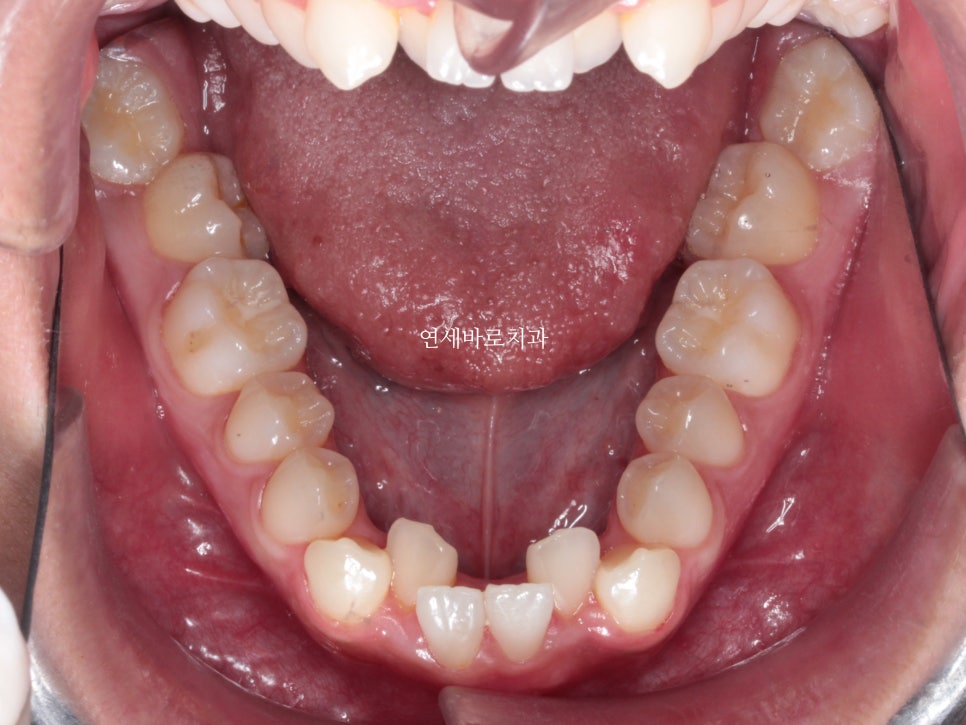

또한 위아래 덧니가 심했어요.

위쪽 2개 치아의 발치 후 교정치료를 진행했습니다.

위쪽은 발치를 해야하기 때문에, 그리고 어금의 개선이 오래걸리기 때문에 아래쪽 장치를 거의 6개월이 지나서 붙이게 되었습니다.

수술 직후의 위아래 모습입니다.